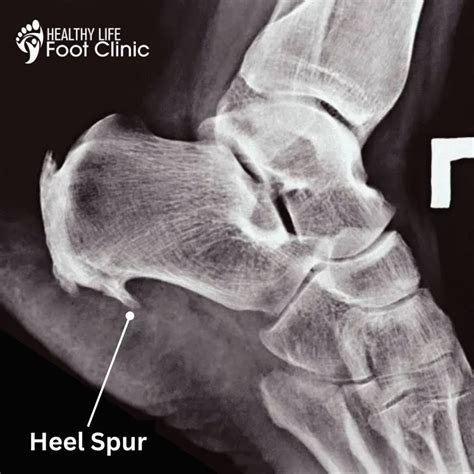

A bone spur, medically referred to as an osteophyte, is a bony projection that develops along the edges of bones. When discussing a bone spur on heel, it is technically known as a calcaneal spur. These spurs occur due to prolonged stress, calcium deposits, or damage to the foot muscles and ligaments. It is important to note that many people have bone spurs on their heels without even realizing it; they are often discovered incidentally during X-rays for other foot-related issues. The pain usually stems not from the spur itself, but from the associated soft tissue damage and inflammation surrounding the area.

If you are experiencing persistent heel pain, it is essential to consult with a podiatrist or orthopedic specialist. They will typically perform a physical examination, checking for areas of tenderness and assessing your gait. To confirm the presence of a bone spur on heel, a doctor will almost always order an X-ray. The X-ray provides a clear image of the heel bone, allowing the physician to visualize the size and location of any bony growth and rule out other potential causes of your pain, such as stress fractures or nerve entrapment.

• bone spur on heel xray